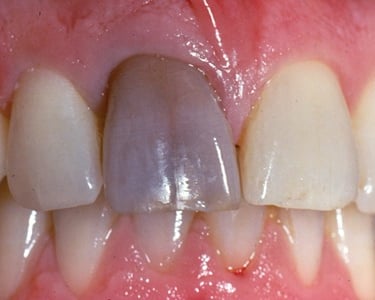

Necrosis Pulpar

La necrosis pulpar es la muerte de la pulpa dental, generalmente como resultado de una pulpitis no tratada.

Los pacientes pueden no sentir dolor, pero el diente puede cambiar de color y presentar mal olor.

Esto puede llevar a una infección del tejido circundante. Es crucial tratarlo con un tratamiento de conducto para evitar la propagación de la infección.